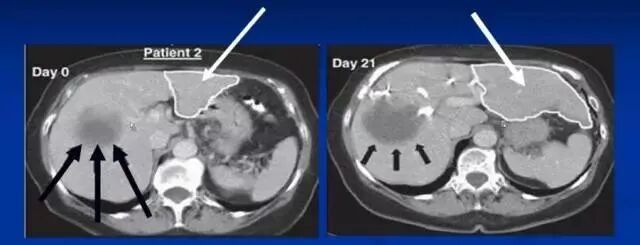

国外质料:执行肝癌(肝右叶)部分肝切除患者,术前给予干细胞治疗(肝左叶),21天后肝左叶成倍增大